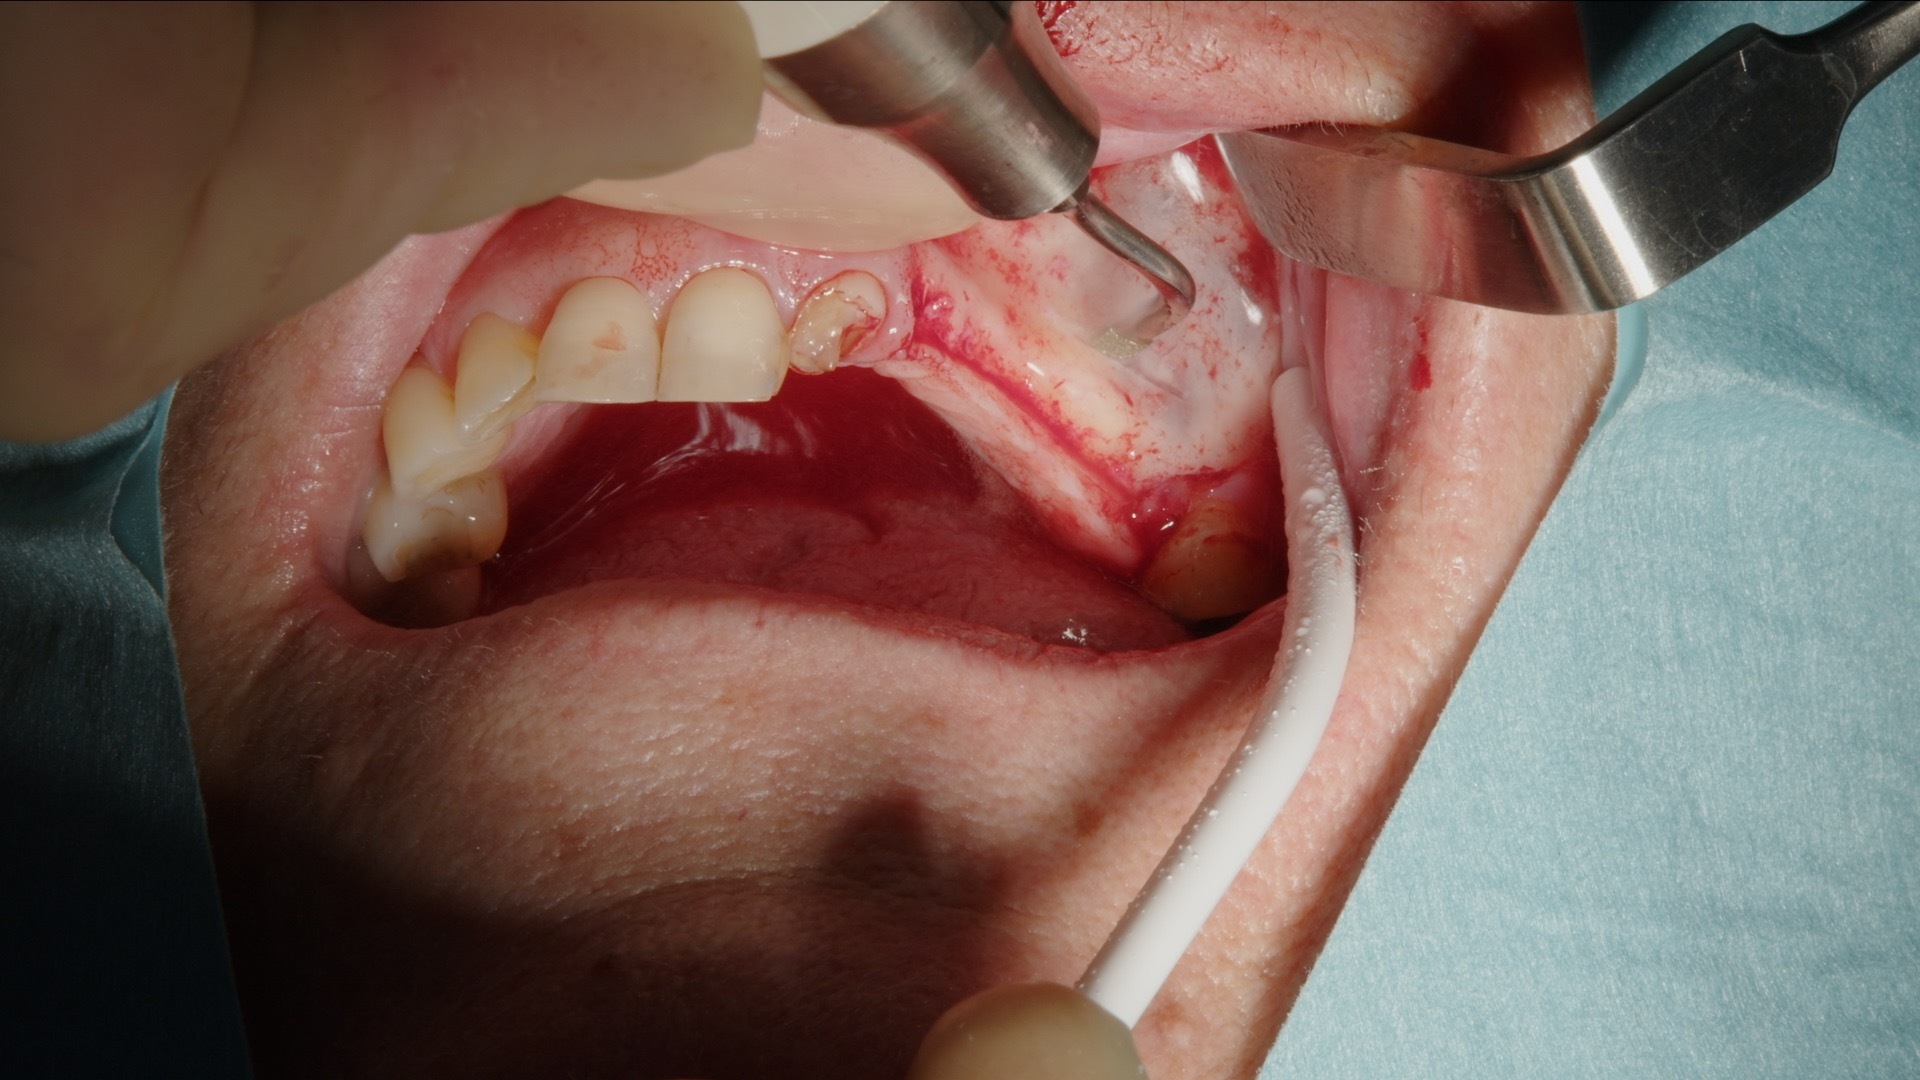

1. Incisjon og lappepreparering før etablering av lateralt vindu.

2. Preparering av lateralt vindu med Acteon Piezo Cube og diamantspiss.

Det laterale vinduet prepareres konsekvent med Acteon Piezo Cube og diamantspiss. Den piezoelektriske teknologien muliggjør selektiv benbearbeiding med høy presisjon og minimal risiko for skade på bløtvev og sinusmembran. Instrumentet er ergonomisk, lett å manøvrere og gir god taktil kontroll, noe som bidrar til en effektiv og trygg prosedyre.